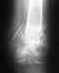

Длительность операции или слово "рядовая" не несут никакой смысловой нагрузки - неизвестно, какой по форме перелом, насколько точно сопоставлены отломки , где находится пластина, сколько винтов какого диаметра насколько надежно ее фиксируют, восстановлена ли форма вилки сустава, и т.д. и т.п.

Слова о том, что Вам что-то важно знать, не заменяют необходимую для содержательного ответа исходную информацию. Которой располагают врачи, участвовавшие в операции, видевшие рентгенограммы до и после операции, которые видели состояние проблемного отдела конечности.